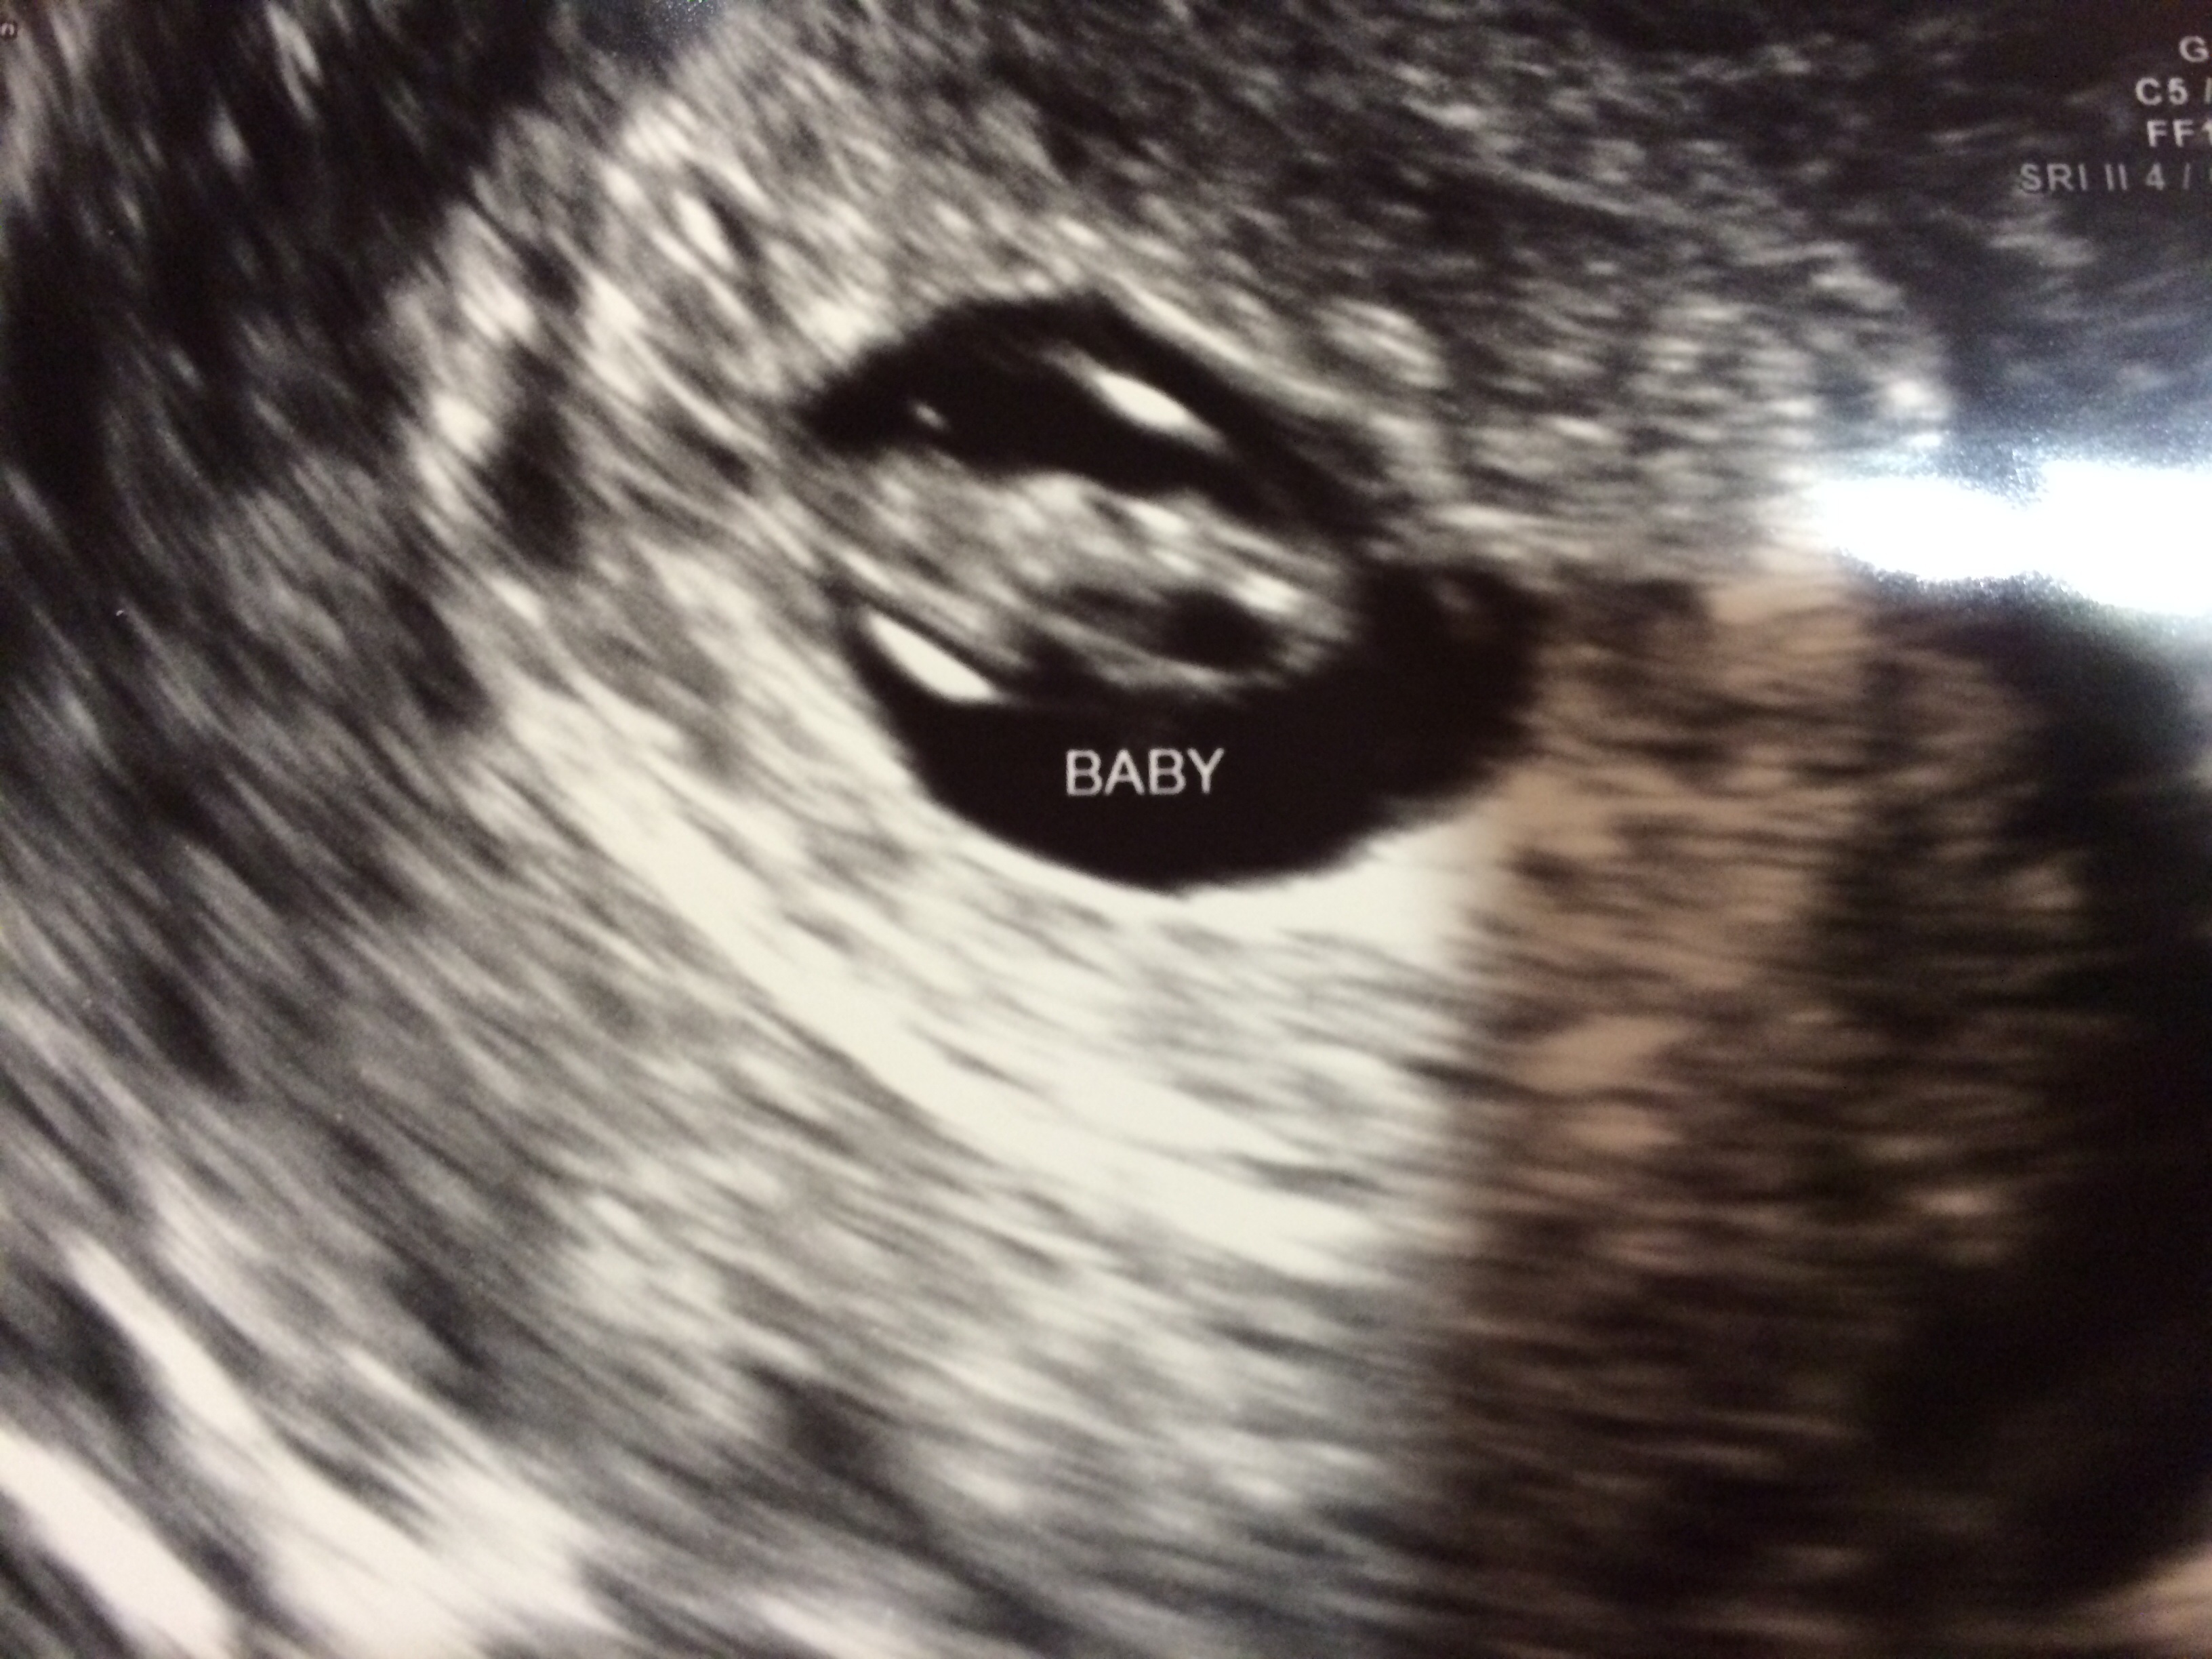

Re: Saw a fluttering heart